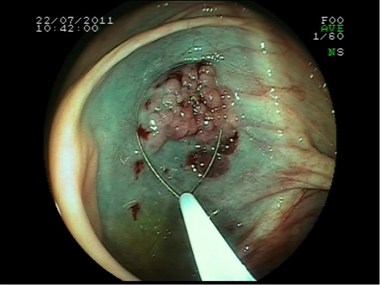

Polipectomía

Escara post polipectomía